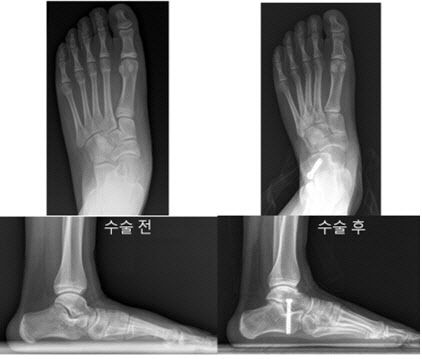

대표적으로 시행되는 ‘종골 연장술’은 뒷꿈치뼈(종골)를 절골한 뒤 뼈를 이식해 아치를 복원하는 수술로, 한 번의 수술로도 지속적인 교정 효과를 얻을 수 있다. 또 다른 수술법인 ‘종골 정지술’은 나사 1개를 삽입해 평발을 교정하는 방식으로, 보다 간단한 수술이 가능하다는 점이 특징이다. 두 수술 모두 평발 교정에 효과적인 것으로 알려져 있지만, 실제 환자 데이터를 바탕으로 두 수술법의 치료 결과를 비교한 연구는 거의 없었다.

종골 정지술’을 받은 12세 환아의 수술 전(좌)과 수술 3년 후(우) 방사선 및 발 사진. 수술 후 발의 정렬이 정상에 가깝게 교정됐으며, 아치 또한 회복되어 평발 변형이 효과적으로 교정된 모습을 확인할 수 있다. |